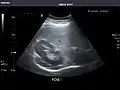

Spleen